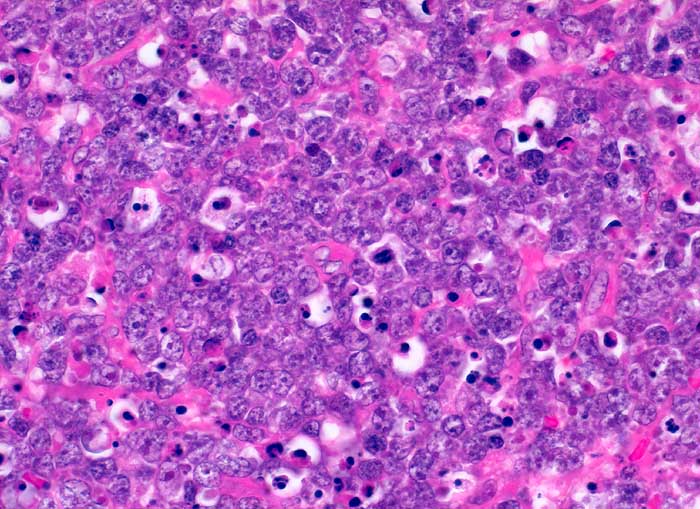

Burkitt Lymphom (WHO)

Blastenrasen aus mittelgrossen monomorphen Blasten. Mitosen und zahlreiche Apoptosen weisen auf die hohe Proliferationsaktivität hin.

Die Tumorzellen sind positiv für den Pan-B-Zell-Marker CD20, sie zeigen darüberhinaus eine starke Expression von CD10 (Calla) sowie von bcl-6. Negativ ist bcl-2. Diagnostisch entscheidend der Proliferationsmarker MIB-1 (Ki-67), welcher in 100% der Tumorzellen nukleär stark positiv ist.

Verdacht auf Lymphom der linken Tonsille

Histologie

400